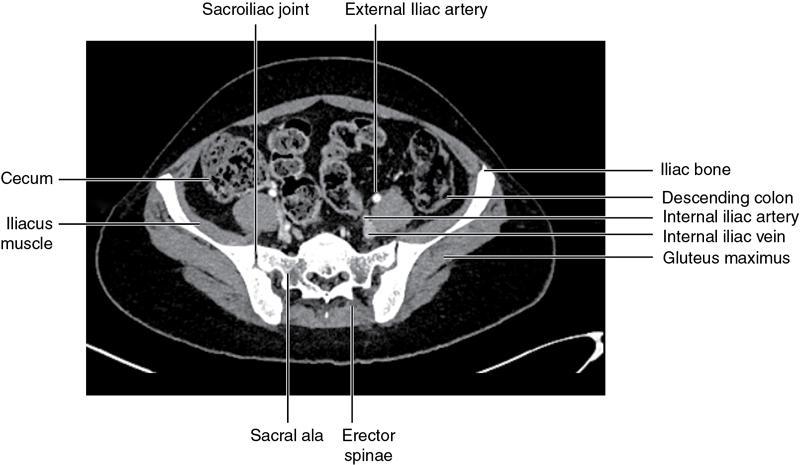

CROSS SECTIONAL ANATOMY OF ABDOMEN Satya Jha NORMAL ANATOMY OF ABDOMEN AND PELVIS Amandeep Singh The two major surfaces: The anterior and posterior layers of the coronary ligament converge on bare area (not covered by peritoneum). Its right and left margins form the right and left triangular ligaments. The right triangular ligament extends toward the diaphragm and separates right subphrenic space from right subhepatic space. The left triangular ligament gives tracts extending to the diaphragm and falciform ligament and does not compartmentalize the left subphrenic space. Ligamentum teres or the obliterated umblical vein is contained in falciform ligament which attaches the liver to anterior abdominal wall. The main portal vein, the proper hepatic artery and the common bile duct are contained within investing peritoneal folds of hepatoduodenal ligament at the porta hepatis (Fig. 7.2.2.1). Liver is divided into eight segments which are functionally independent and have their own vascular supply and biliary drainage. Arterial circulation: The branches of the hepatic artery accompanying the portal veins. Hepatic venous system: The right, middle, and left hepatic veins draining into IVC (Figs. 7.2.2.2 and 7.2.2.3). The gallbladder is a blind pear-shaped muscular membranous sac which is an embryologic derivative of the foregut, is a pouch lying along the undersurface of the liver. The gallbladder fossa is located in the plane of the interlobar fissure, which lies between the right and left hepatic lobes. Its major function is to store and concentrate bile which is produced by the liver. It measures approximately 4 cm in diameter when it is normally distended. Gallbladder is a smaller tubular structure in contracted state. The normal gallbladder wall thickness ranges from 1 to 3 mm. The gallbladder is divided into the fundus, body and neck. Infundibulum is present in the region of neck of the gallbladder, which is called the Hartmann pouch, where gallstones are usually impacted. Intrahepatic biliary radicles (IHBRs) scattered throughout the liver get confluent towards the hilum. They unite to form the right and left main hepatic ducts which further unite to form common hepatic duct (CHD) at the hilum. Common bile duct is formed by the union of cystic duct with common hepatic duct. The main pancreatic duct is joined with the common bile duct to form the ampulla of Vater at the major duodenal papilla (Figs. 7.2.2.4 and 7.2.2.5). Pancreas is located in anterior pararenal space of retroperitoneum anterior to perirenal (Gerota’s) fascia and posterior to parietal peritoneum. It is divided into head, uncinate process, neck, body and tail from right to left. Pancreas lies anterior to portal vein, which marks the point of transition between the body and neck. The region between head of pancreas and second and third parts of duodenum is known as the pancreatic groove. In postnephrectomy cases or with agenesis of kidney or ectopic kidney, pancreas moves posteriorly to partially fill in the empty renal fossa; its soft tissue density should not be mistaken for recurrent tumour. It is located in the pancreatic groove and is bounded superiorly by the duodenal bulb, laterally by second portion of duodenum, inferiorly by third portion of duodenum, medially by superior mesenteric vein and anterior to inferior vena cava. It is a wedge or wedge shaped lying posterior to superior mesenteric artery and vein. It is an imaginary junction between the head and body and lies directly over the junction of the splenic vein and superior mesenteric vein. It is located posterior to the lesser sac and anterior to the aorta, left adrenal gland, left kidney, and renal vessels and runs obliquely upward to the left of the superior mesenteric vessels. It is situated median to the colonic flexure and anterior to the left kidney. It is located in close proximity to the splenic hilum without a notable relation with the body of pancreas. It is seen anterior to the left kidney and median to the colonic flexure. The distal part of the tail passes between the peritoneal layers of the splenorenal ligament (Fig. 7.2.2.6 and 7.2.2.7).